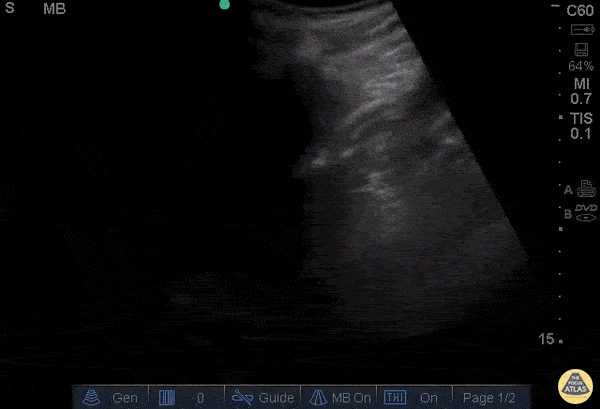

Renal/GU - Moderate Hydronephrosis

66 yo M with hx of congenital single kidney and prostate cancer presents with suprapubic discomfort x 1 week. Found to be in urinary retention. POCUS allows grading of hydronephrosis based off of the severity of the dilation of the renal pelvis and calyces. Here we see dilated pelvis, ballooning calyces, and cortical thinning. This represents Grade 3, moderate hydronephrosis. Grade 4, severe, would demonstrate further atrophy and loss of borders, occurs with severe hydronephrosis. Rushabh Shah, MD, MBA and Maria-Pamela Janairo, MD - Kings County/SUNY Downstate Emergency Medicine